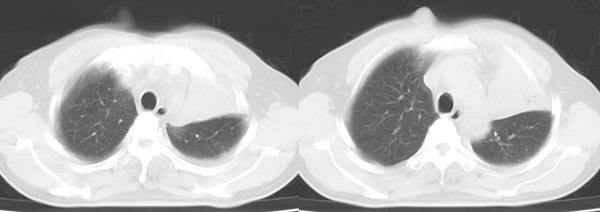

以下是引用dyqct在2006-4-1 22:20:00的发言:[br]左肺上叶明显萎陷、实变,支气管大部通畅,部分扩张,部分壁似见串珠状钙化。主动脉弓旁见肿大淋巴结。纵隔左移。左侧胸壁后缘见新月形高密度,边界清楚。[br] 考虑:1、左肺上叶肺不张伴支气管扩张(牵拉性),可能为支气管内膜结核所致。[br] 2、左侧少量胸腔积液。[br]

以下是引用piao001在2006-4-2 14:13:00的发言:[br]左肺上叶不全性不张,其内见钙化及扩张支气管,结合病史,考虑支气管内膜结核。建议支气管镜明确检查。